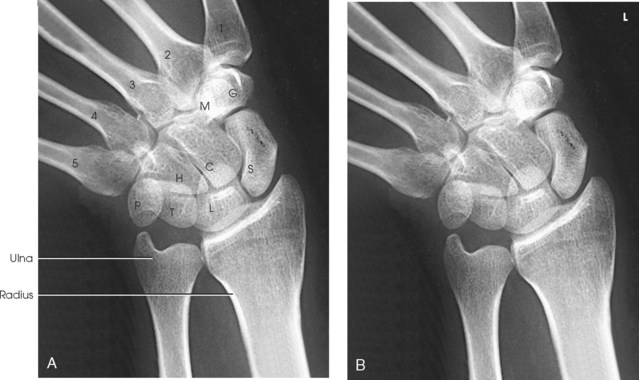

The wrist has eight carpal bones, which are fitted closely together and arranged in two horizontal rows (see Fig. 4-1). The carpals are classified as short bones and are composed largely of cancellous tissue with an outer layer of compact bony tissue. These bones, with one exception, have two or three names; this atlas uses the preferred terms (see box). The proximal row of carpals, which is nearest the forearm, contains the scaphoid, lunate, triquetrum, and pisiform. The distal row includes the trapezium, trapezoid, capitate, and hamate.

Each carpal contains identifying characteristics. Beginning at the proximal row of carpals on the lateral side, the scaphoid, the largest bone in the proximal carpal row, has a tubercle on the anterior and lateral aspect for muscle attachment and is palpable near the base of the thumb. The lunate articulates with the radius proximally and is easy to recognize because of its crescent shape. The triquetrum is roughly pyramidal and articulates anteriorly with the hamate. The pisiform is a pea-shaped bone situated anterior to the triquetrum and is easily palpated.

Beginning at the distal row of carpals on the lateral side, the trapezium has a tubercle and groove on the anterior surface. The tubercles of the trapezium and scaphoid constitute the lateral margin of the carpal groove. The trapezoid has a smaller surface anteriorly than posteriorly. The capitate articulates with the base of the third metacarpal and is the largest and most centrally located carpal. The wedge-shaped hamate exhibits the prominent hook of hamate, which is located on the anterior surface. The hamate and the pisiform form the medial margin of the carpal groove.

The carpals articulate with each other, the metacarpals, and the radius of the forearm. In the carpometacarpal (CMC) articulations, the first metacarpal and trapezium form a synovial saddle joint, which permits the thumb to oppose the fingers (touch the fingertips). The articulations between the second, third, fourth, and fifth metacarpals and the trapezoid, capitate, and hamate form synovial gliding joints. The intercarpal articulations are also synovial gliding joints. The articulations between the lunate and scaphoid form a gliding joint. The radiocarpal articulation is a synovial ellipsoidal type. This joint is formed by the articulation of the scaphoid, lunate, and triquetrum, with the radius and the articular disk just distal to the ulna (Fig. 4-9, C).

Structures shown: A PA projection of the carpals, distal radius and ulna, and proximal metacarpals is shown (Fig. 4-70). The projection gives a slightly oblique rotation to the ulna. When the ulna is under examination, an AP projection should be taken.

Structures shown: The carpal interspaces are better shown in the AP image than the PA image. Because of the oblique direction of the interspaces, they are more closely parallel with the divergence of the x-ray beam (Fig. 4-72).